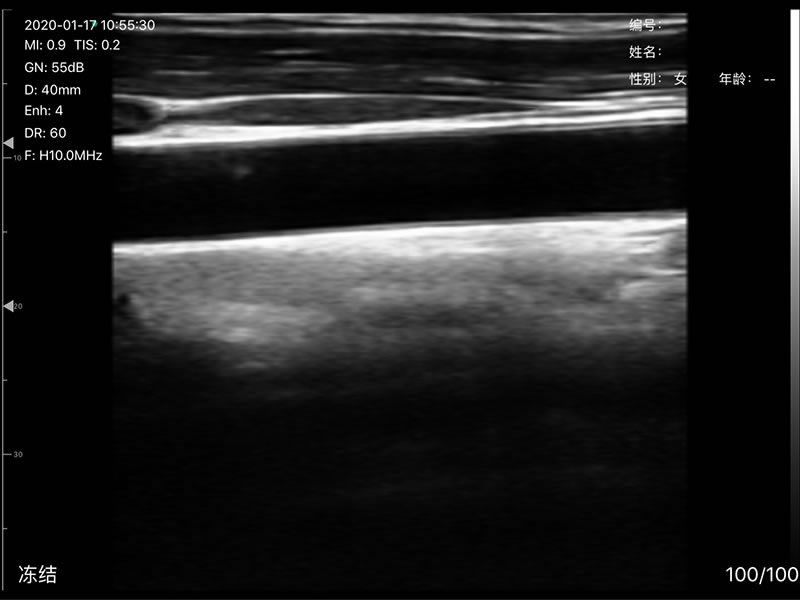

• 探头频率:相控阵2.2/3.6MHz,线阵7.5/10 MHz

• 扫描声头:同时具备微凸、线阵两个声头,并可通过按键快速切换

• 扫描深度:相控阵20-240mm,线阵 20-100mm,可调

• 扫描角度和宽度:相控阵80mm,线阵25mm

• 显示模式:B、B/M、Color、PW、PDI